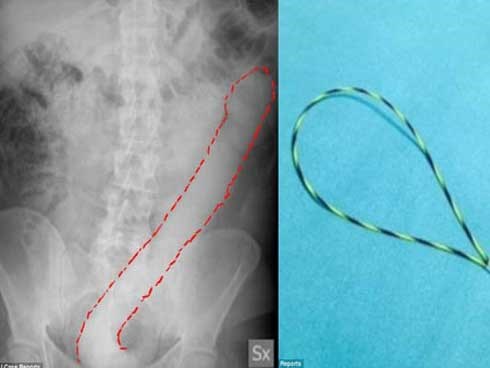

Thử cảm giác lạ bằng dương vật giả 60cm, người đàn ông khóc thét vì không thể rút ra

Đến các bác sĩ cũng phải đau đầu khi nghĩ cách lấy chiếc dương vật giả có độ dài 60cm ra khỏi đại tràng của người đàn ông 31 tuổi.